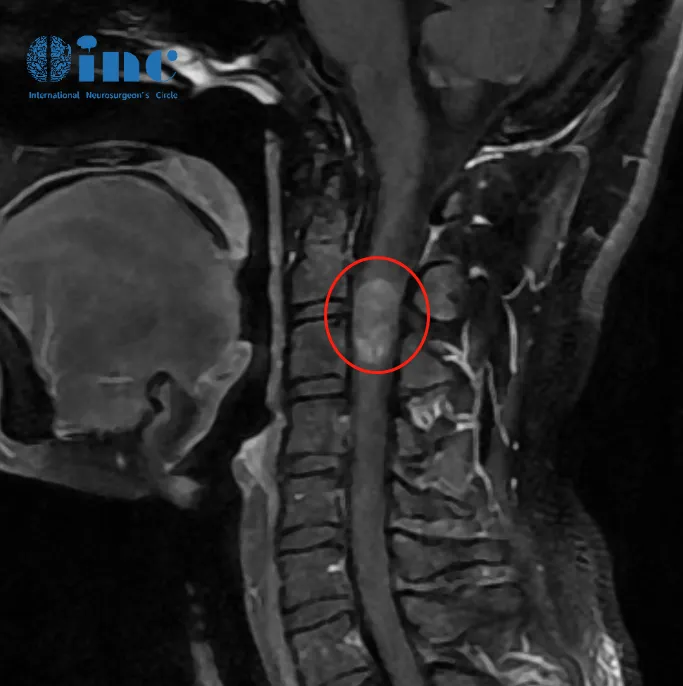

2021年7月行增强磁共振提示C3水平占位,直径7mm。当地医院排除炎性病变。因考虑到手术风险大,未作手术治疗。

2022年6月磁共振提示大小约8*12*14mm。2022年10月磁共振提示8*12*19mm。虽然这颗颈髓内的肿瘤仅仅只有1cm左右花生大小的肿瘤,但是伴随而来的症状越发严重,除了手臂、指尖、腿部等肢体麻木、接踵而来的背部疼痛让她夜不能寐,正处盛年的她笼罩在病魔的阴影之下。肿瘤持续进展,年轻的潇潇不愿意继续坐以待毙。